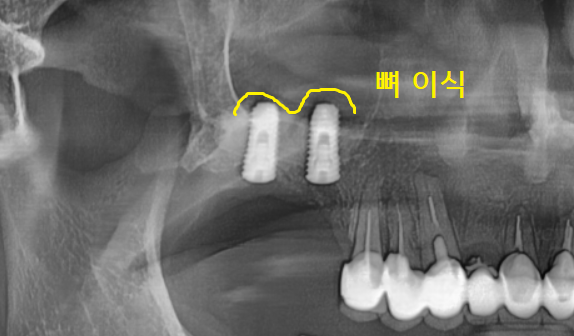

23.09.08

명일동 치과 상악동 거상술 후

예쁘게 돔 모양으로 뼈 이식이 된 것이 확인되시죠?

상악동을 들어 올린 후 잇몸뼈를 이식했기 때문에

충분히 기다려주었습니다.